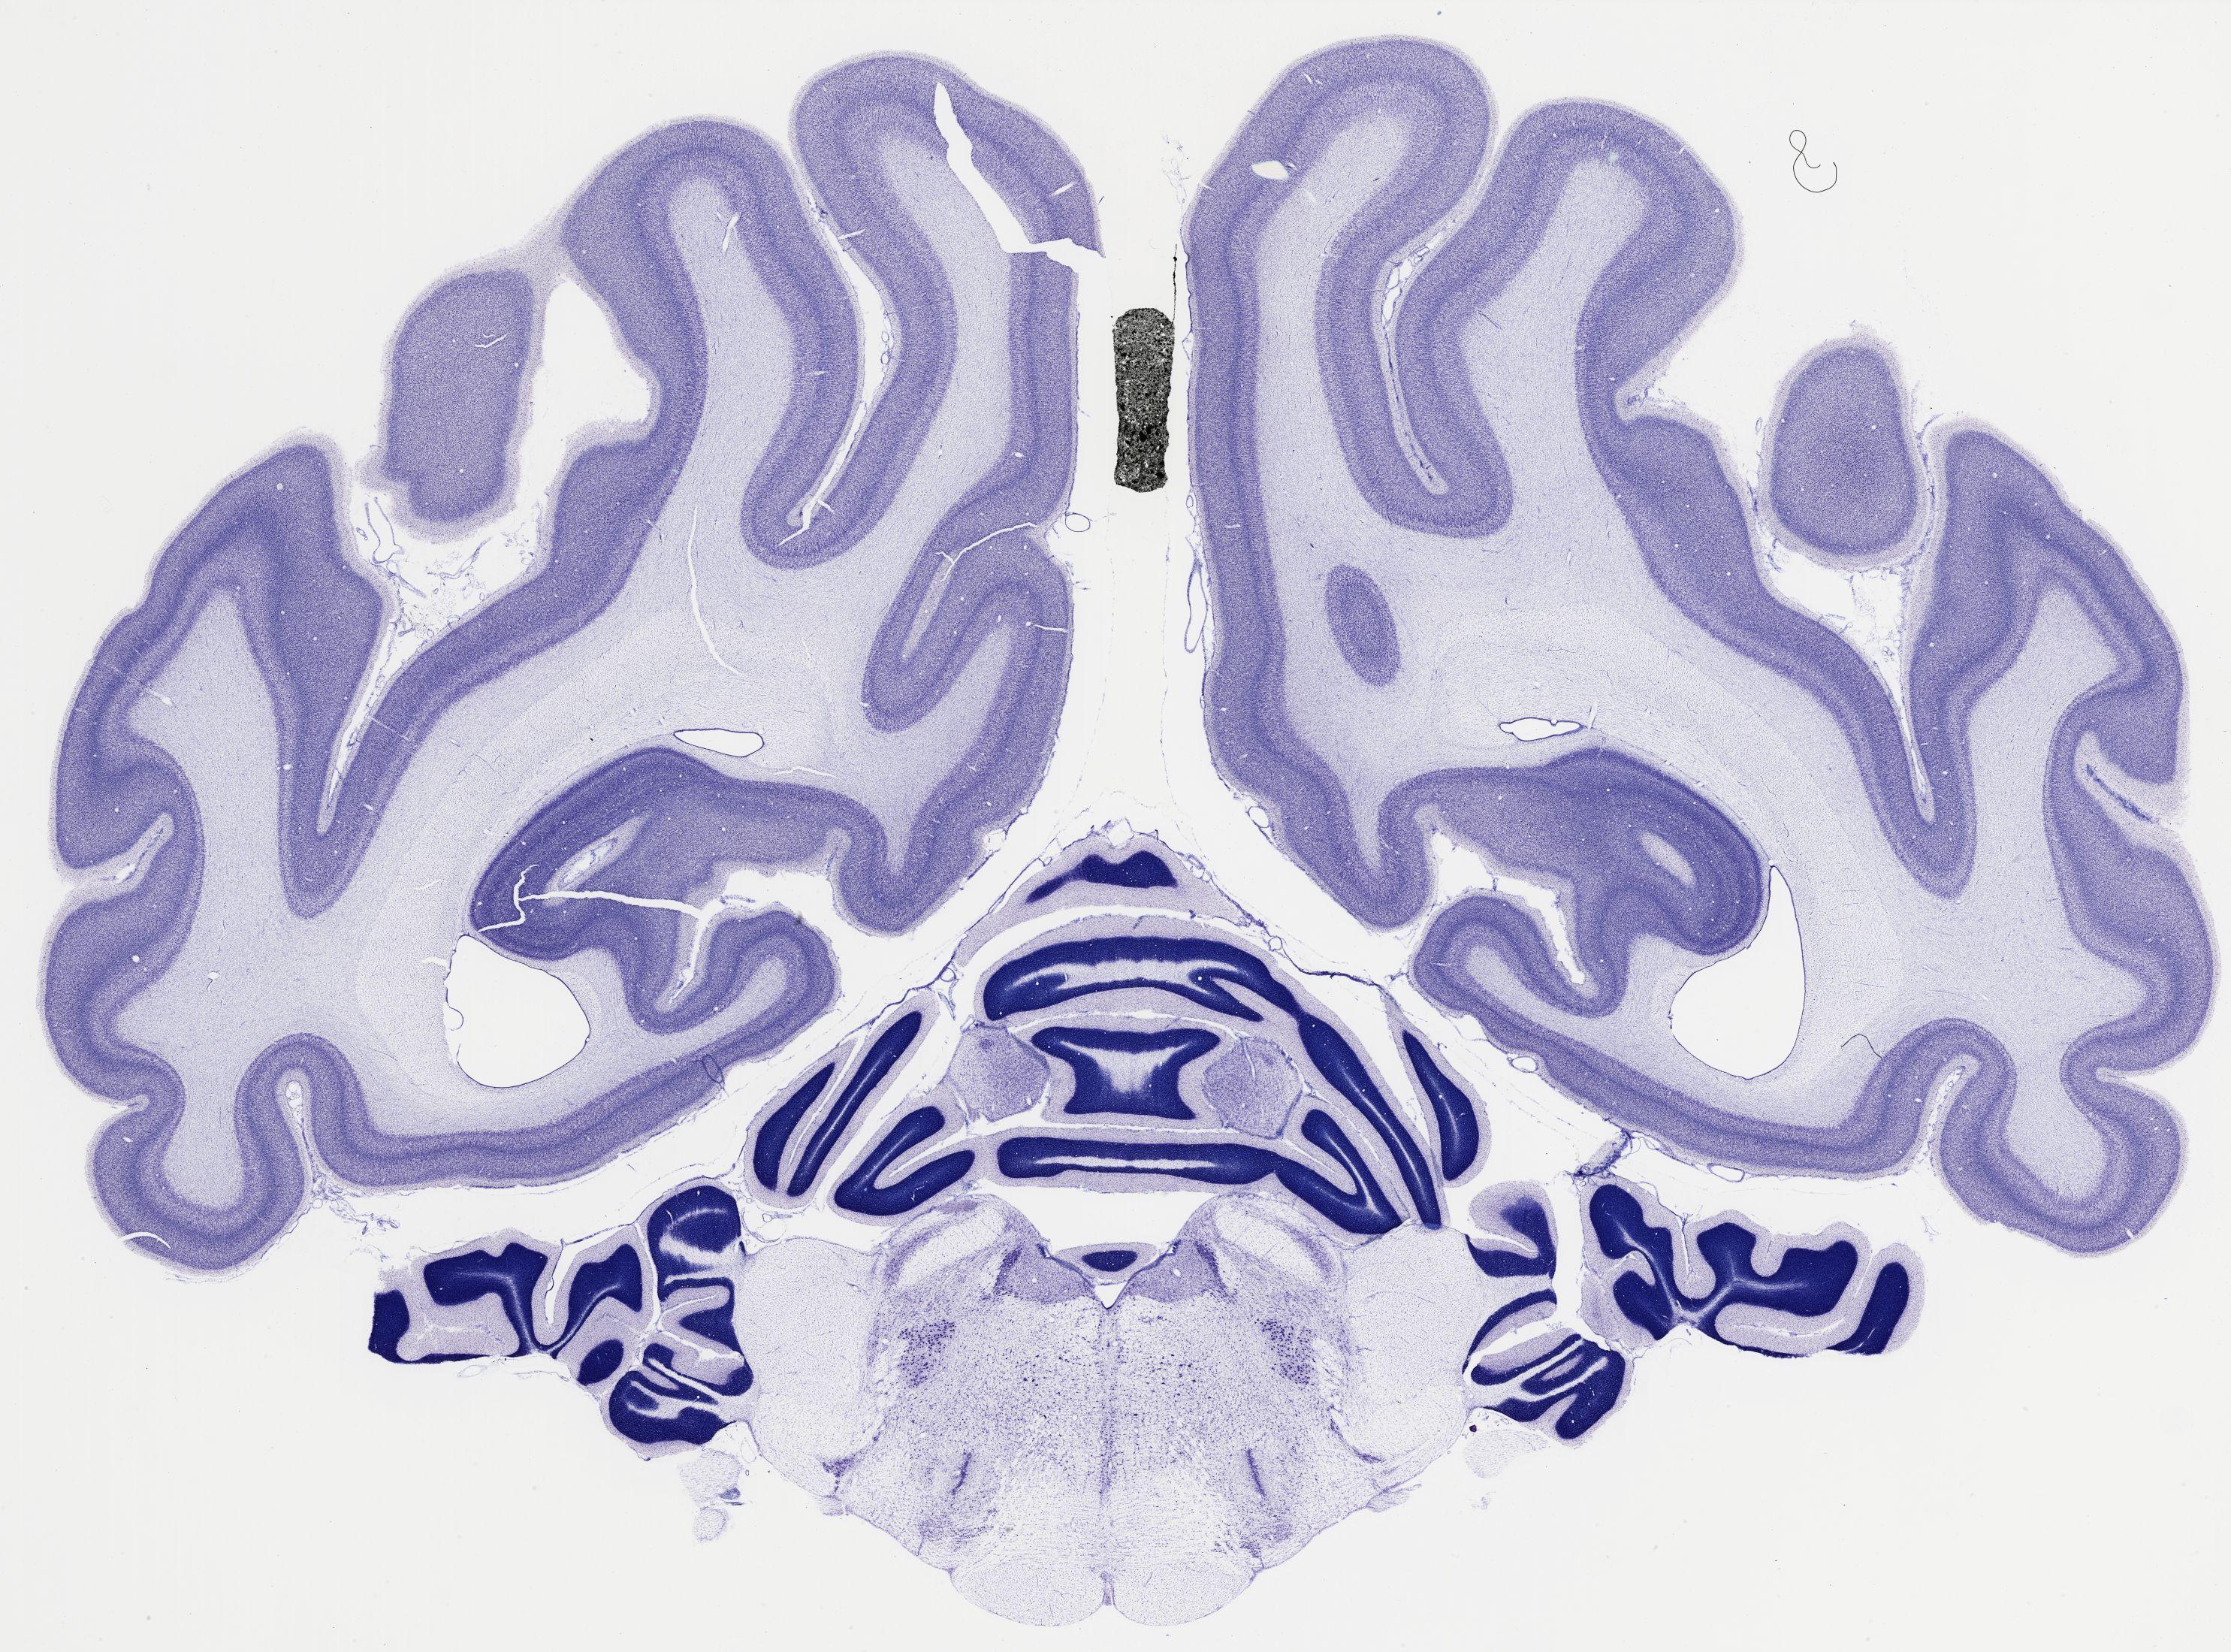

thumbnail

521